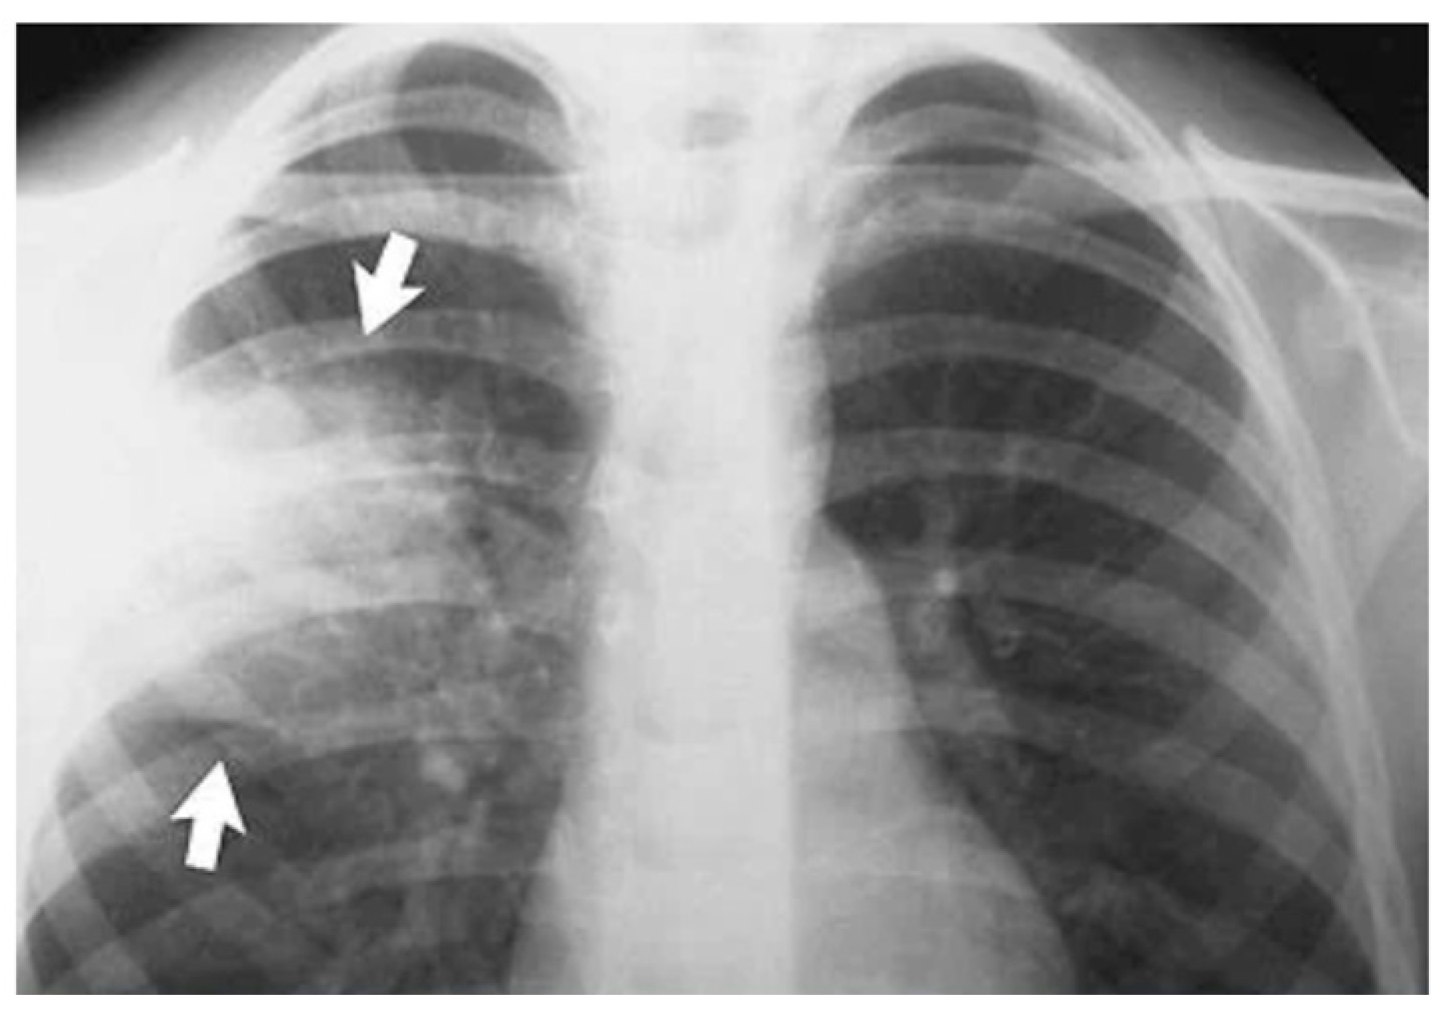

1.1. Pneumonia Imaging Modalities

- Variability in Image Quality: Chest X-ray image quality can vary significantly, making it challenging to identify subtle abnormalities.

- Overlapping Features: Pneumonia patterns may overlap with other lung conditions, leading to misinterpretations.

- Size and Location of Infection: The size and location of pneumonia can affect its visibility in X-rays.